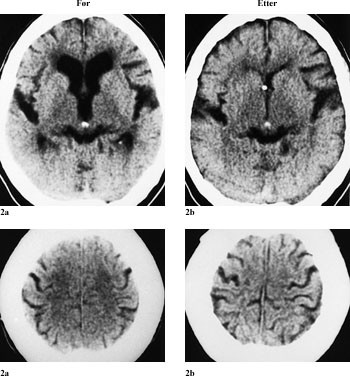

I tillegg til de kliniske symptomer baseres diagnosen normaltrykkshydrocephalus på funnene ved cerebral computertomografi (CT) (2 – 5). En CT-undersøkelse av hjernen er fortsatt en god screeningmetode, der store ventrikler, utplanert kortikalt relieff og periventrikulær lavattenuering er typisk for normaltrykkshydrocephalus (3).

Behandlingen ved normaltrykkshydrocephalus går ut på å drenere cerebrospinalvæsken via et rørsystem til bukhulen, ventrikuloperitoneal shunt (fig 1 – 3), for å normalisere og stabilisere de intrakraniale trykkforhold.